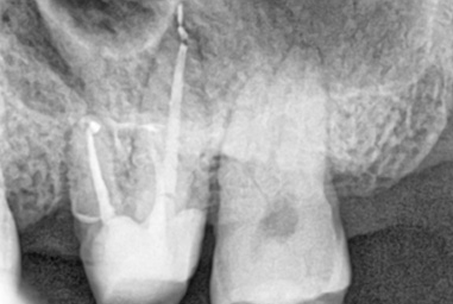

위 사진들은 현직 치과의사들이

저희 웃는얼굴 치과에서 치료 받은 실제 사례들입니다.

비 전문가 눈에는 그냥 흔한 엑스레이 사진일 뿐이겠지만

치과의사들이라면 알아챕니다.

저 치료가 얼마나 난이도 있는 치료였는지,

얼마나 정성이 들어갔는지를 말이지요.